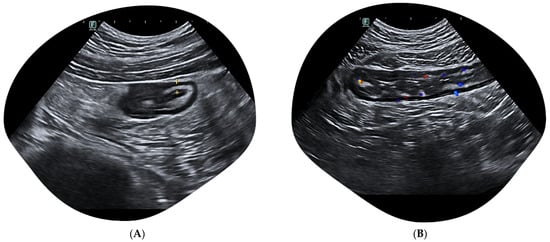

2.2. The Challenge of Rectum Evaluation